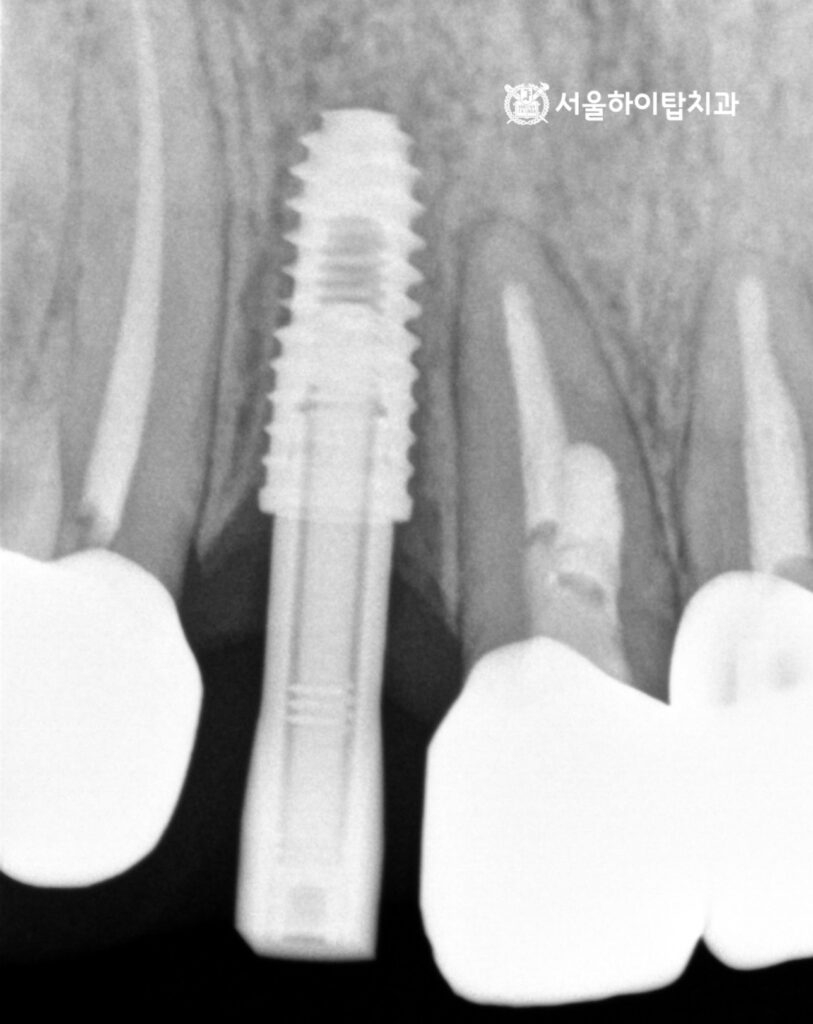

초진 구강 내 모습과 PA(치근단 방사선)사진을 살펴보겠습니다.

치관(치아 머리)이 통째로 파절된 모습을 볼 수 있습니다.

PA 사진에서 근관 내부가 전용 충전재인 가타퍼차로 채워져 있는 것을 확인할 수 있는데,

이를 통해 과거 신경치료를 받은 치아임을 알 수 있습니다.

즉, 신경치료 후 치아를 보호하기 위해 씌워졌던 크라운이 있었으나,

이번 파절로 인해 치관이 치근에서 완전히 분리된 상태임을 알 수 있습니다.

위 엑스레이 사진을 살펴보면,

전치부 치아 특성상 치조골 폭이 다소 좁음에도 불구하고,

앞서 진행한 가상 시뮬레이션을 기반으로 안전하고 정확한 위치에

임플란트가 식립된 모습을 확인할 수 있습니다.

백운역 치과 에서 PA 사진으로 확인해도,

주변 인접 치아나 치주 조직에 손상 없이 정확하게 식립된 모습을 확인할 수 있습니다.